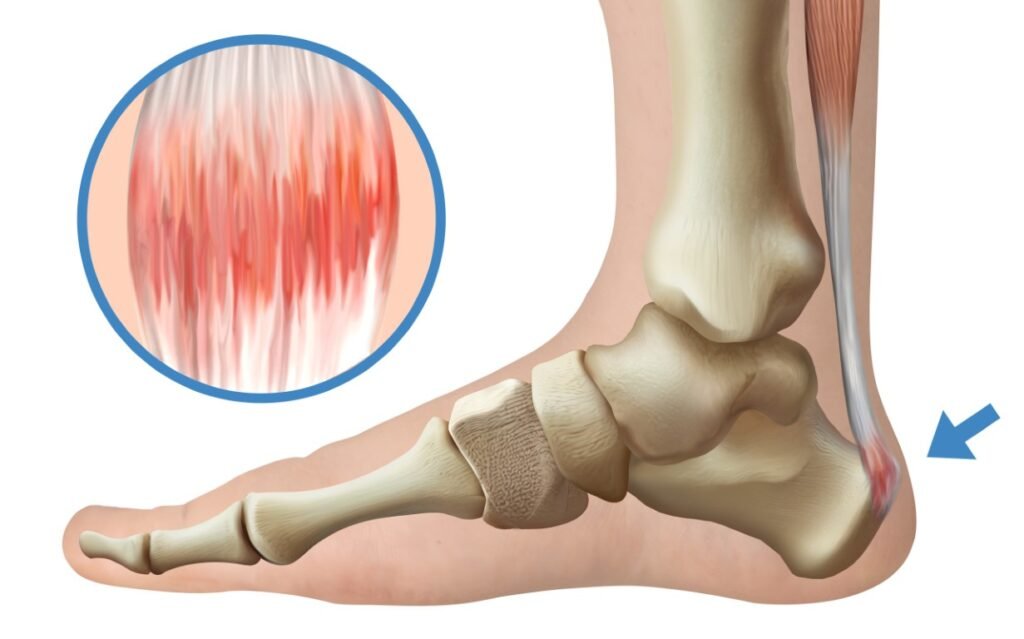

- التهاب وتمزق وتر أكيليس (وتر العرقوب): من أكثر إصابات الأوتار شيوعًا، ويصيب لاعبي كرة القدم والجري، وينتج عن الإجهاد المتكرر أو القفز والجري المكثف.

إصابات الأوتار تحتاج إلى تعامل دقيق وصبر في العلاج، لأن العودة السريعة للنشاط الرياضي دون تأهيل كافٍ تزيد من خطر تكرار الإصابة وتحولها إلى حالة مزمنة.

يرتكز علاج إصابات الأوتار على تقليل الأحمال البدنية، العلاج الطبيعي المتخصص، وتمارين الإطالة والتقوية التدريجية.

علاج إصابات الأوتار

وفي الحالات المزمنة، قد يتم اللجوء إلى وسائل علاجية متقدمة لتحفيز التئام الأوتار، مع متابعة طبية دقيقة لضمان استعادة الأداء الرياضي بأمان.